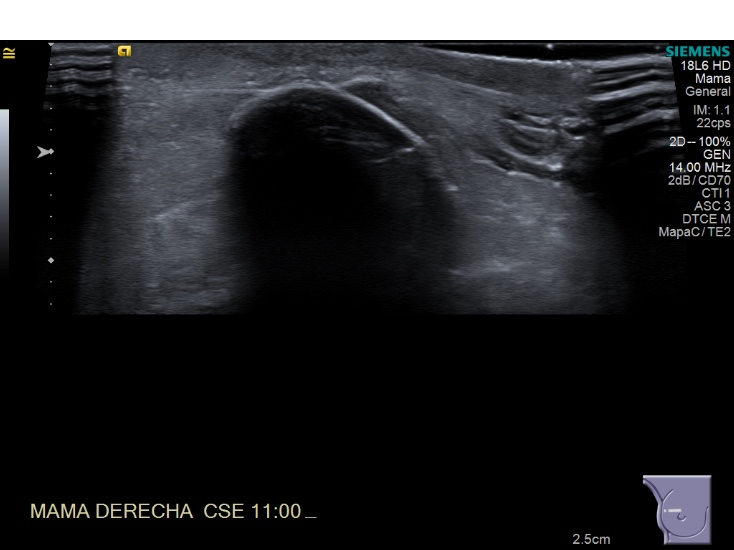

Crioablacion de tumor en mama derecha